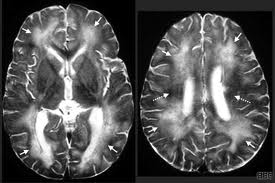

(vi)Thêm vào đó,tiền sử đau sưng khi đi lại, đau rễ dây thần kinh hay hình ảnh não bằng X quang gợi ý xuất huyết trong não giống các rãnh là các bằng chứng hỗ trợ cho Gnathostomiasis.